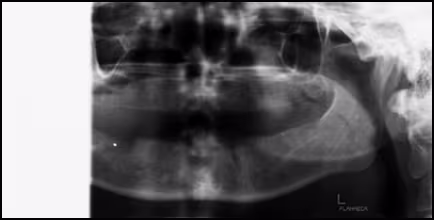

Figure 60. Incomplete Panoramic Image. Shoulder contact on the patient’s right side caused the machine to stop resulting in a partial image.

Figure 61. Distorted Panoramic Image. Shoulder contact on the patient’s right side caused the patient to move in response producing wave-like distortion and cut-off the right ramus.